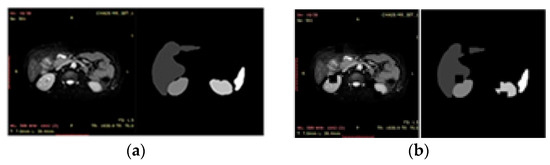

2.1. Data Source of Organ

The tomographic abdominal organ dataset Chaos [38] is a medical imaging dataset focusing on abdominal organs such as liver, kidney, and spleen structures. This dataset is prominent in the adjunctive treatment of diseases such as acute liver failure, impaired renal function, and abdominal aneurysms. Abdominal imaging is an essential subfield of diagnostic radiology, which plays a vital role in daily control and postoperative follow-up. Imaging modalities of Chaos dataset images are mainly composed of electron computed tomography (CT) and magnetic resonance imaging (MRI). The CT data images were used in 40 cases, with the task of single-organ segmentation of the abdominal liver, and the MRI data images are used in 80 points, with the mission of multi-organ segmentation of the abdomen. Imaging modalities of the MRI data images are divided into longitudinal relaxation imaging (T1) and transverse relaxation imaging (T2), with T2 imaging being practical in showing lesion areas, edema, and tumors. T2 imaging effectively shows lesion areas, edema, and tumors and usually provides better soft tissue contrast than T1 imaging. For the above reasons, this experiment selected T2 imaging MRI medical image maps for abdominal 4-organ image segmentation; the organs are the spleen, left kidney, right kidney, and liver. Partial T2 dataset, partial T2 dataset corresponding labels, and labeled organ location schematics are shown in Figure 1a–c, respectively.

Figure 1.

(a) Partial T2 dataset; (b) Partial T2 dataset corresponding labels; (c) Labeled organ location schematics.